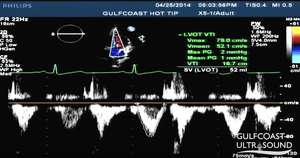

- Aortic valve area (AVA) requires LVOT diameter (D) and velocity time integral (VTI) at LVOT and AV in the continuity equation

- More reliable than CW doppler peak velocity

- Obtain LVOT diameter just apical to AV in PSL at maximal systole

- Obtain the following in apical view at the aortic valve as parallel to flow as possible to avoid falsely low values

- AV VTI (continuous wave doppler), gate at tips of AV opening in systole, tracing below the line in systole

- LVOT VTI (pulse wave doppler), gate in LVOT just apical to AV, tracing below the line in systole

AVA Continuity Equation

LVOT Diameter (D) in cm

LVOT VTI in cm

AV VTI in cm